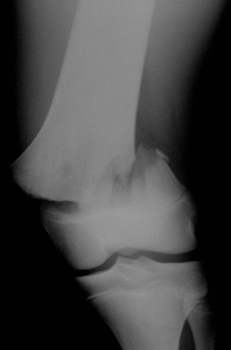

Oberschenkelfraktur bei einem 17-jährigen

postoperativer Befund |

belastbar nach 8 Tagen